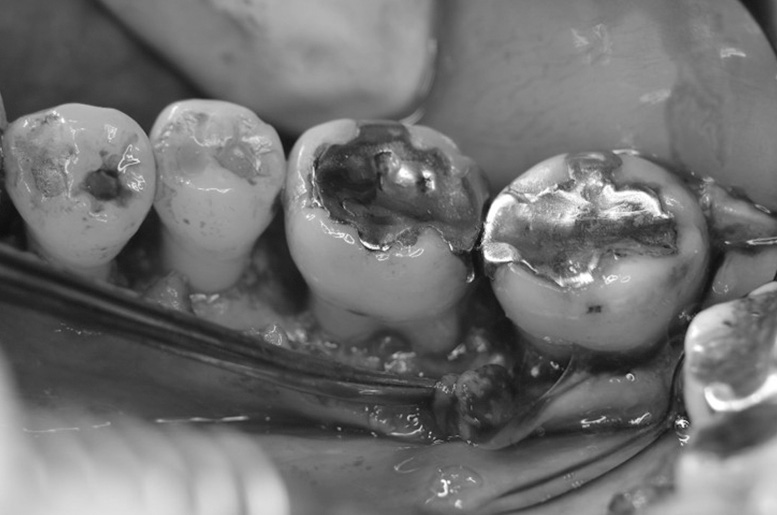

歯周再生療法 精密根管治療 歯周矯正治療 ジルコニアセラミック治療